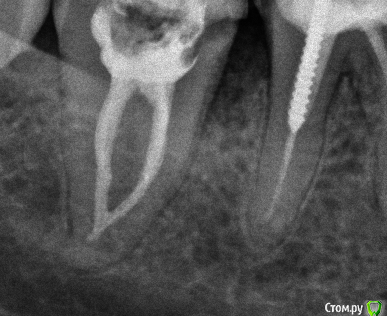

Shaid Опубликовано 16 декабря, 2014 Поделиться Опубликовано 16 декабря, 2014 Нарыл фотку(извиняюсь за качество)http://s009.radikal.ru/i309/1412/56/8804e380b022.jpg 1 Ссылка на комментарий

SSTi Опубликовано 16 декабря, 2014 Автор Поделиться Опубликовано 16 декабря, 2014 44 зуб страшилка. Все стандартно. Упор 45. 6 Ссылка на комментарий